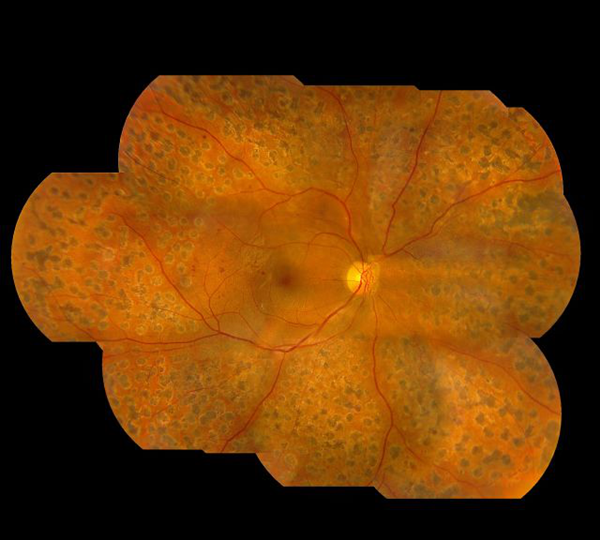

视网膜病变依据变病的特性和水平,临床医学上把它分成两种类型六期,前三期为单纯性型视网膜病变,又叫情况期或者非繁衍期;后三期则为繁衍型视网膜病变,又叫繁衍期或新生儿毛细血管期。

假如实际到临床表现,在查验眼眸时,大家会发觉:

1.眼眸具体表现为有微神经纤维瘤和血点;

2.会出现强制外渗及流血斑;

3.主要表现为柔性外渗及流血斑;

4.主要表现为眼底黄斑新生儿毛细血管产生和或玻璃体出血;

5.主要表现为新生儿毛细血管产生并由此可见化学纤维繁衍;

6.则在所述基本上出現视网膜剥离。

视网膜病变在初期,也就是前三期,糖尿病患者们一般沒有一切觉得,沒有一切病症。因此 非常容易被忽视,视网膜病变也因而被称为双眼的“隐形杀手”。当变病加剧出現眼底黄斑浮肿时,糖尿病患者就很有可能会出現视物模糊。但由于能够是单眼病发,眼睛视力下降并不大,也不适合造成病人高度重视。

仅有当玻璃体出血较多时,才会显著危害眼睛视力,可出現眼下阴影、视野缺损,乃至彻底视力模糊看不到。

情况严重失明

假如眼底黄斑浮肿蔓延到到黄点,糖尿病患者轻则会出現视力模糊形变,比较严重的还因黄点囊样浮肿,造成 不可避免的眼睛视力危害。而到视网膜病变末期的时候通常因比较严重流血、视网膜脱落,造成 永久性失明。

此外,若产生视网膜或房角新生儿毛细血管,还可出現新生儿血管性青光眼症状,可有无法操纵的眼睛痛、头疼、恶心干呕等。角膜水肿丧失偿还,眼睛神经危害,会造成 永久性失明痛疼。

不难看出,视网膜病变伤害十分的大,其引起的无法操纵的玻璃体出血、视网膜脱落、新生儿血管性闭角型青光眼和比较严重的糖尿病患者黄斑水肿是造成 糖尿病患者失明的关键缘故。